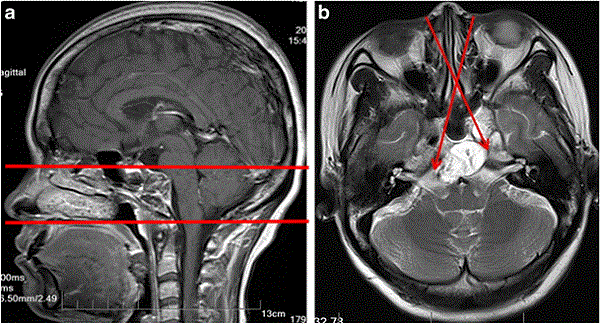

看东西复视,眼睛有点斜,两只眼睛看东西的颜色不一样……一名28岁的青年男性因为这些症状前去就医,通过核磁共振检查发现原来是斜坡脊索瘤。斜坡脊索瘤属于颅底脊索瘤,颅底脊索瘤本身就是一种恶性且少见的肿瘤,其特点是术后复发风险高。由于斜坡脊索瘤对放疗和化疗不敏感,所以手术是治疗的关键方法,并且手术切除的程度与肿瘤复发和预后密切相关。

目前的研究表示,初次尝试手术提供了实现完全切除的更佳机会。脊索瘤仍然是一个挑战性的病变,但通过内窥镜鼻内入路,可以提高切除率,降低发病率。治疗斜坡脊索瘤应根据检查结果和肿瘤的位置特征选择较合适的手术方法,因此,在较大限度地提高肿瘤切除程度的同时,可以设计合适的个性化手术方法,可以较大限度地减少手术创伤。所以选择一个有经验和能力的医生也是手术切除率高的关键。